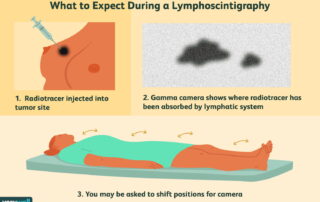

Λεμφοσπινθηρογράφημα

Τι είναι οι λεμφαδένες; Οι λεμφαδένες είναι μικρά στρογγυλά όργανα που αποτελούν μέρος του λεμφικού συστήματος [...]